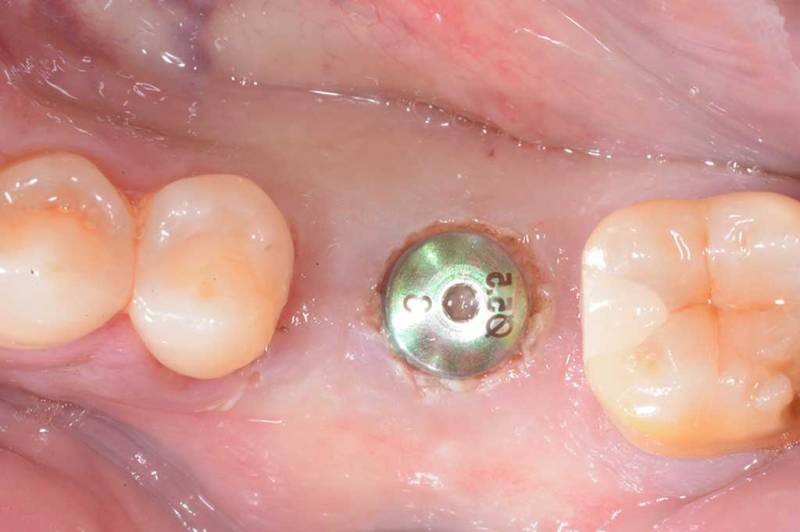

微創植牙術前

微創植牙術中

微創植牙術後